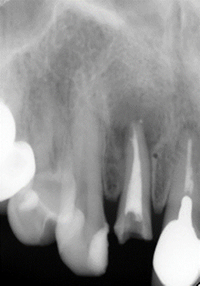

術直後のレントゲンです。

治療後

病巣(赤丸)は消失しています。